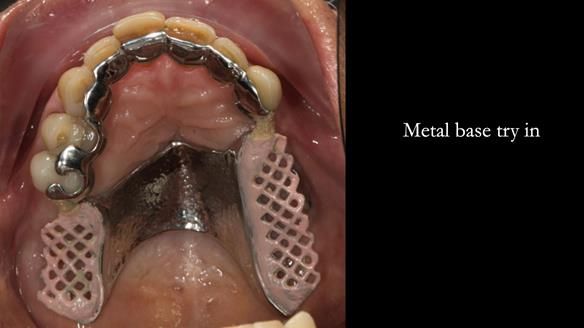

The upper jaw

In the upper arch:

- a failing upper left tooth supporting a bridge was removed

- an implant-supported bridge on the upper right was dismantled

A metal-based upper RPD was made,

with metal backings incorporated to future-proof the design

should further teeth fail.

Looking back, we would make this denture more hygienic now. The design and finish would be more refined and delicate, particularly when compared with the upper metalwork, which was made later using Chris Hesketh’s chrome work. I will discuss this in detail at the study club.